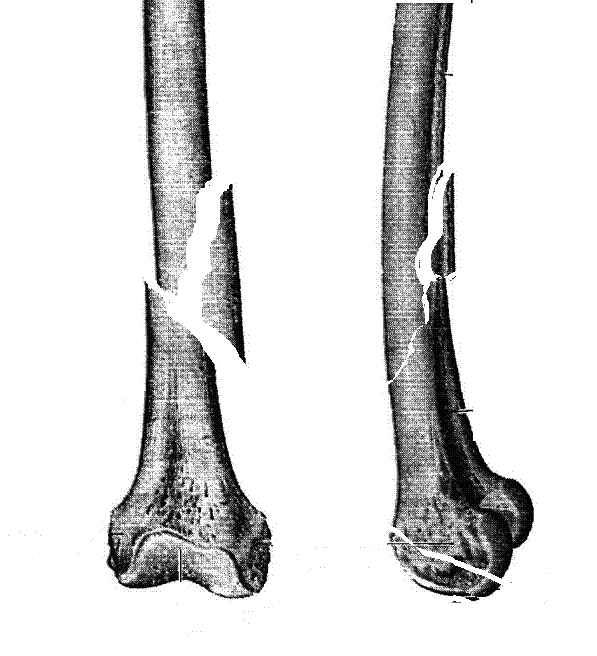

Женщина 66 лет 15.10.2006 получила закрытый окольчатый перелом правой бедренной кости в с\з-н\з со смещением отломков. 17.10.2006 доставлена в травм.отделение (2-е суток лежала одна дома). При поступлении наложено скелетное вытяжение за бугристость большеберцовой кости - груз 5 кг, затем увеличен до 7 кг. Схематические рисунки контрольных Р-грамм прилагаются (прошу прощения за отсутствие Р-грамм, постараюсь "донести").В связи с отсутствием материальных средств и "удовлетворительным" положением отломков решено было скелетное вытяжение оставить как окончательный метод лечения. На 20.11.2006 отека правого бедра нет, пальпаторно умеренная болезненность в месте перелома, крепитации отломков нет (и по-видимому не было изначально),подвижность в месте перелома сохранена, но не выражена. Двигательных, чувствительных и трофических расстройств правой нижней конености нет. Уважаемые коллеги! Какова дальнейшая тактика в случае вероятной интерпозиции тканей? Больная "кровавое" оперативное лечение не "потянет" материально. Даст ли в данном случае что-то АВФ закрыто?

Нету там интрепозиции. Если картинка рентгенологическая близка к тому, что Вы прислали на рисунке.